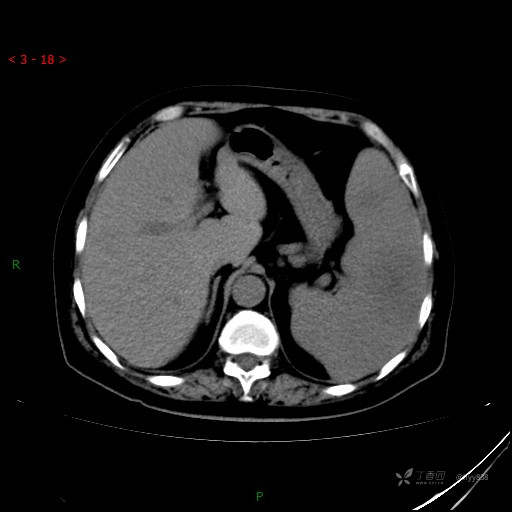

上腹部CT平扫